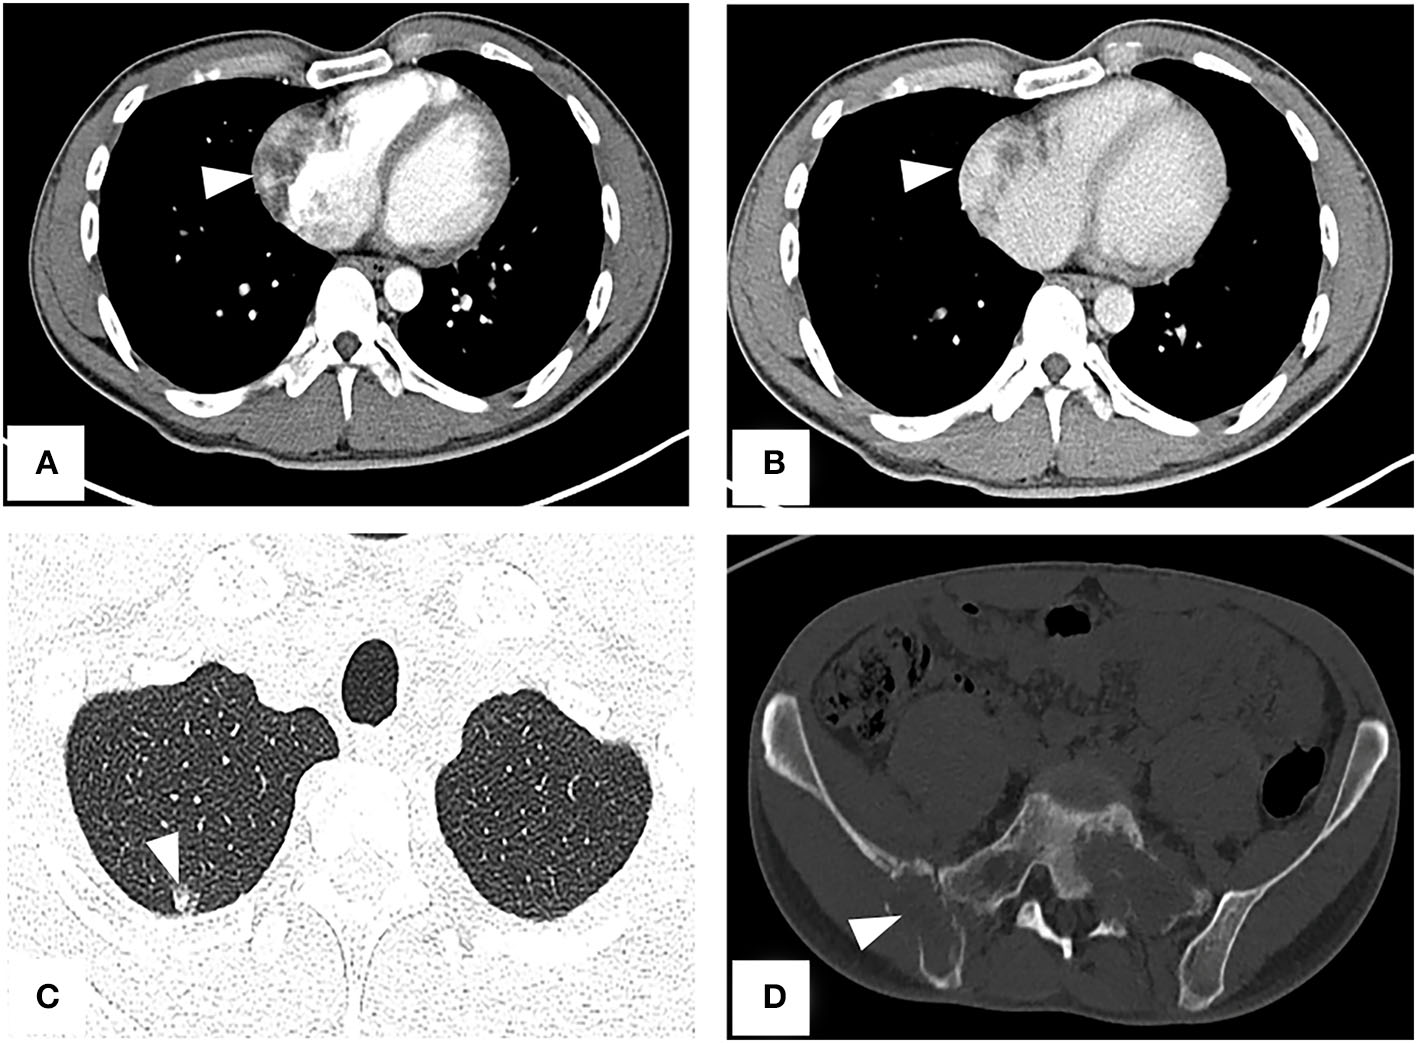

A CT examination from the chest to the pelvis was performed, which revealed a right atrial mass, multiple small ground-glass pulmonary nodules, and bone destructions (Figures 1A–D). Transthoracic echocardiography (TTE) showed an ill-defined hypoechoic mass of approximately 3.8 cm × 2.3 cm, attached to the lateral wall of the right atrium. Cardiac MRI (CMRI) exhibited a right atrial tumor and multiple pulmonary lesions. On steady-state free precession (SSFP) cine imaging planned in the four chambers, the tumor showed isointense (Figure 2A). On T2-short tau inversion recovery (STIR) sequence images, the tumor displayed high-signal intensity (Figure 2B). On enhanced MRI, the tumor showed arterial heterogeneous enhancement and progressive but incomplete enhancement in the delayed phase (dynamic acquisition) (Figures 2C,D). The patient was referred for 18F-fluorodeoxyglucose (FDG) positron emission tomography-CT (PET-CT) for further characterization of the cardiac mass and systemic evaluation. PET-CT images demonstrated that the right atrial tumor had intensely increased FDG uptake (standardized uptake value, SUVmax, 8.4) with signs of pulmonary and bony metastases (Figure 3). These preoperative images characterized the mass as highly suspicious for a malignant cardiac tumor with multiple metastases.

Figure 1

CT from chest to pelvis with enhancement shows right atrial tumor, small ground-glass pulmonary nodule, and bone destructions. (A) Arterial phase imaging reveals a filling defect in the right atrium (arrowhead). (B) Venous phase imaging shows the tumor inhomogeneously enhancing (arrowhead). (C) A lung window image shows a metastatic nodule in the upper right lung. (D) Bone destructions in the right ilium and sacrum.